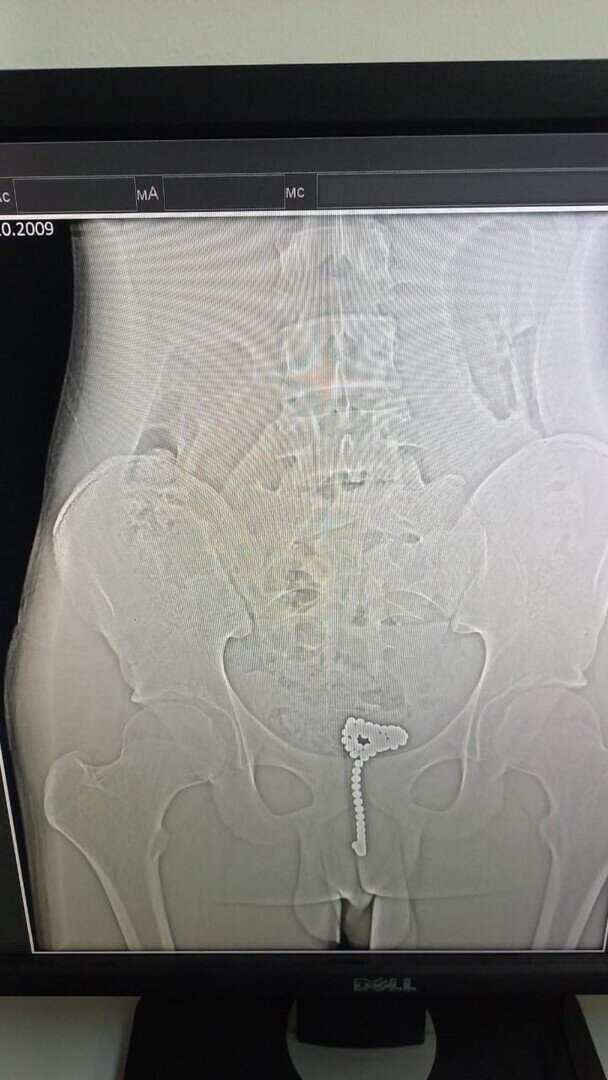

В Новороссийске из тела 14-летнего подростка вытащили 40 магнитных шариков В детском хирургическом отделении спасли молодого человека, который решил экспериментировать с собственным телом. Он поместил себе в уретру около 40 магнитных шариков. От этого подростку стало плохо. Его срочно доставили в первую горбольницу. Бригада медиков под руководством заведующего Севака Веляна срочно прооперировала юного пациента. Была выполнена диагностическая уретроскопия с цистоскопией. Извлечь эндоскопически эти шарики не удалось. Пришлось выполнять открытую операцию, которая прошла успешно. Конгломерат магнитных шариков был удален. Юноша сейчас находится на лечении в отделении детской хирургии. Около двух недель после такой «шалости» он пролежит в больнице, сообщили в пресс-службе медучреждения.

Он поместил себе в уретру около 40 магнитных шариков. От этого подростку стало плохо. Его срочно доставили в первую горбольницу.

Бригада медиков под руководством заведующего Севака Веляна срочно прооперировала юного пациента. Была выполнена диагностическая уретроскопия с цистоскопией. Извлечь эндоскопически эти шарики не удалось. Пришлось выполнять открытую операцию, которая прошла успешно. Конгломерат магнитных шариков был удален.